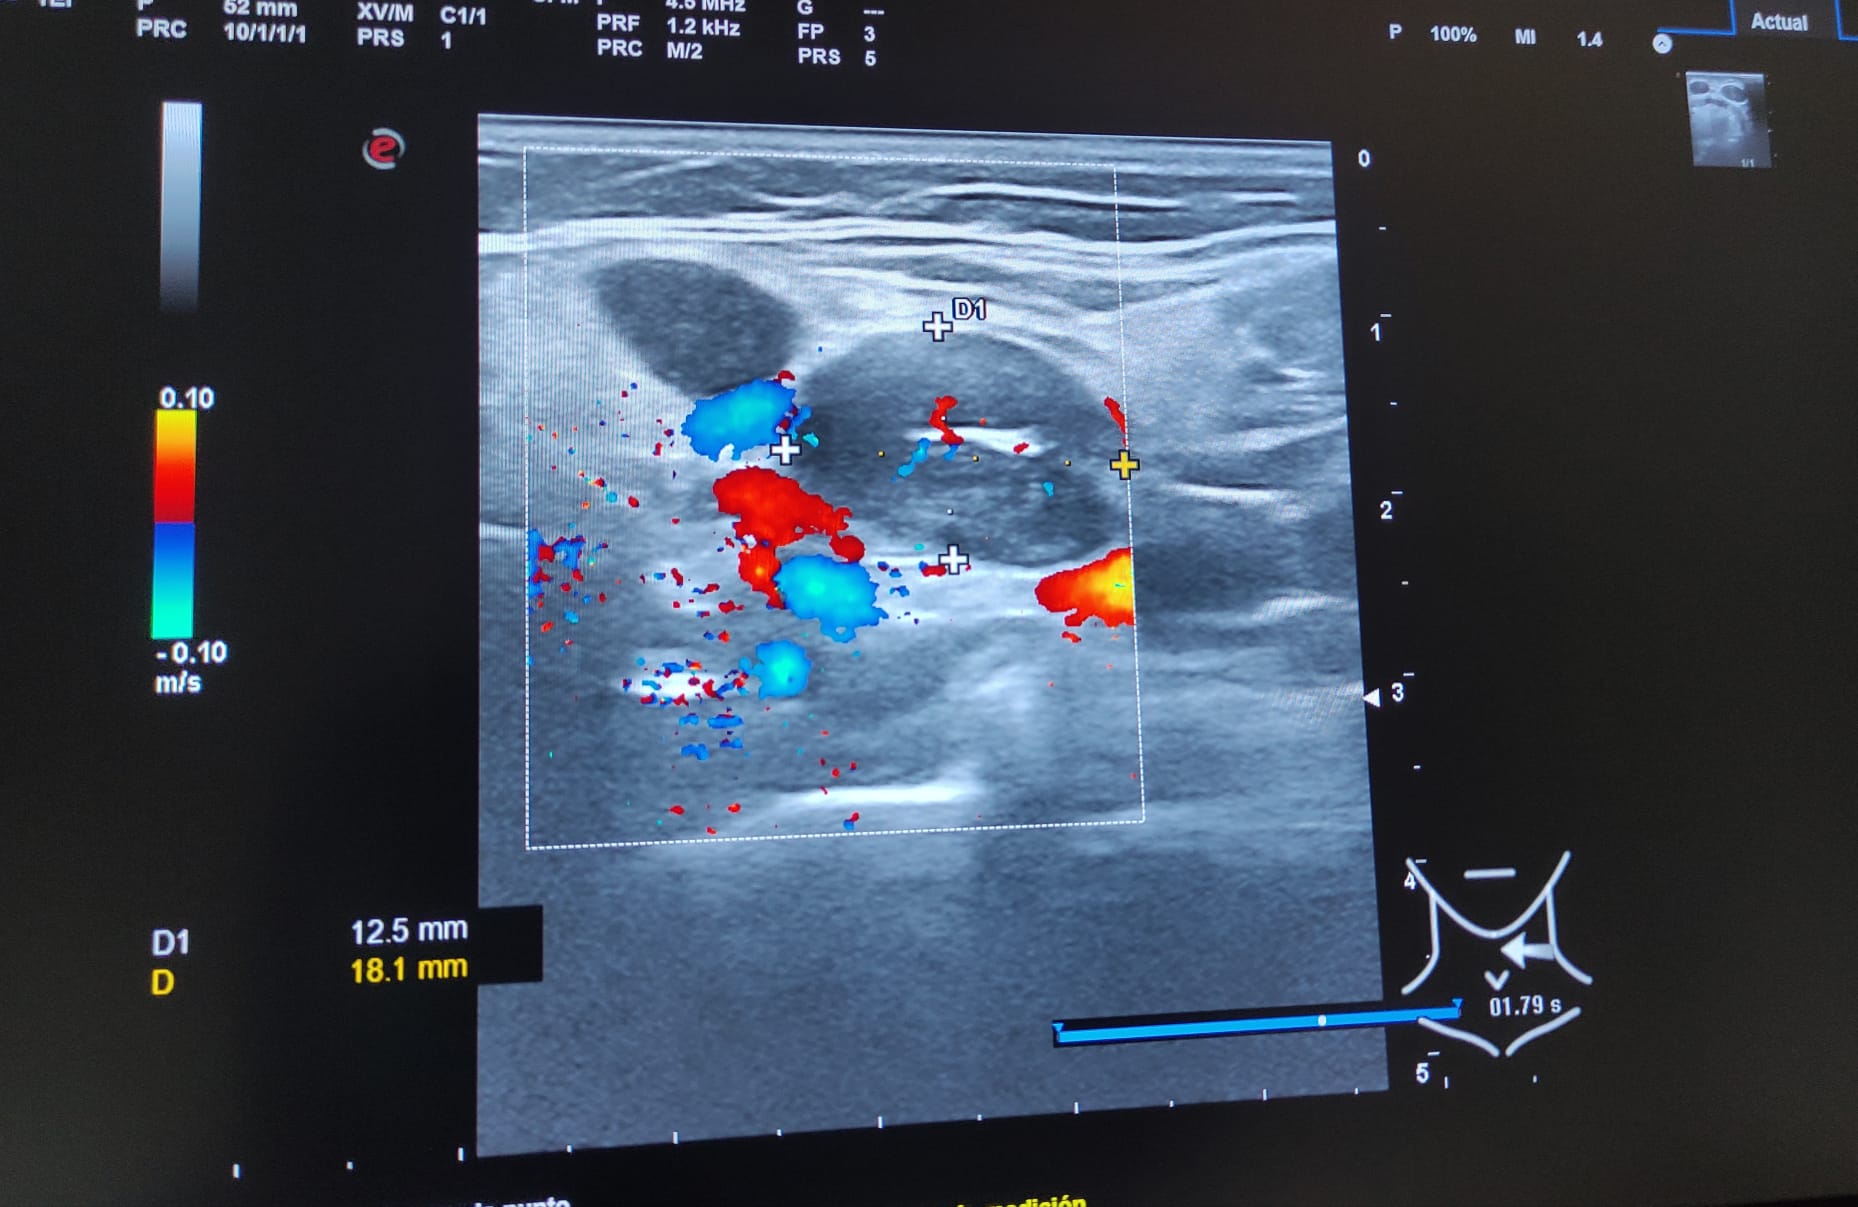

Hallazgos ecográficos

Múltiples adenopatías (más de 12) de varios tamaños siendo la mayor de 2 cm y de morfología redondeada, alguna sin hilio ni centro graso.

A los 3 meses se realiza nueva ecografía sin observar cambios significativos en las adenopatías ya visualizadas. Paciente permanece asintomática.